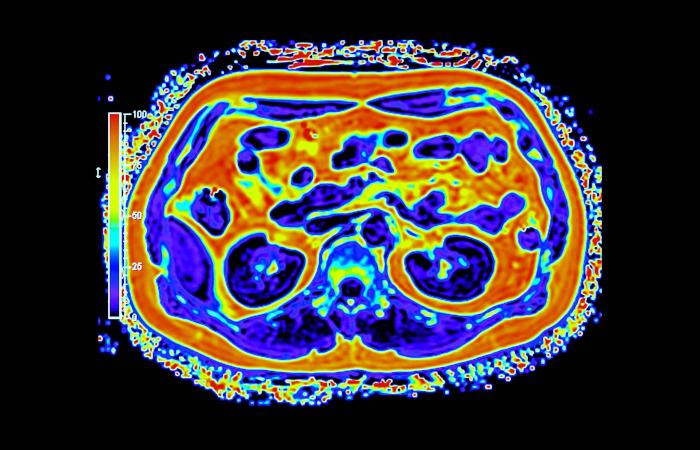

غالباً ما يُتناول تحوّل القطاع الصحي عبر محطات واضحة للعيان، مثل إنشاء مستشفيات جديدة، وإطلاق منصات رقمية، واعتماد أجهزة طبية متقدمة. غير أنّ جانباً أقل ظهوراً وأكثر حسماً يتمثل في بناء بنية تحتية تشخيصية قادرة على دعم الاكتشاف المبكر والطب الدقيق والرعاية الوقائية على نطاق وطني. ويقع التصوير الجزيئي، ولا سيما التقنيات الهجينة، مثل «PET - MRI» في صميم هذا التحول.

وعلى خلاف التصوير التقليدي، يجمع التصوير الجزيئي بين التفاصيل التشريحية والبيانات الوظيفية الآنية، ما يتيح للأطباء رؤية كيفية عمل الأنسجة لا مجرد شكلها. وفي مجالَي الأورام والأمراض العصبية، قد يُحدث هذا الفرق تحولاً في توقيت الاكتشاف أو في تعديل خطط العلاج أو في تجنّب إجراءات غير ضرورية. غير أن توسيع هذه القدرات عبر بلد واسع ومتنوّع جغرافياً يطرح تحديات تتجاوز كثيراً مجرد اقتناء الأجهزة.

أحرزت السعودية تقدماً تدريجياً في نشر أنظمة التصوير المتقدم، بما في ذلك «PET - CT» و«PET - MRI» داخل مراكز طبية كبرى. وبحسب الدكتور سامح الشيخ المدير العام لشركة التصوير الجزيئي والقطاع الطبي بوادي جدة، أثبتت هذه التقنيات قيمتها السريرية عبر الكشف عن انتشار سرطاني أو اضطرابات لم تُظهرها وسائل التصوير التقليدية، ما أتاح تعديل العلاج فوراً في عدد من الحالات.

يواجه التصوير الجزيئي تحدياً يتمثل في التفاوت الإقليمي حيث تتركز الخدمات المتقدمة في المدن الكبرى مقارنة بالمناطق الأخرى (شاترستوك)

قيمة هذه التقنيات لا تكمن في الأجهزة وحدها بل في المنظومة المتكاملة التي تشمل المتتبعات الإشعاعية والكوادر المتخصصة وسلاسل الإمداد (شاترستوك)